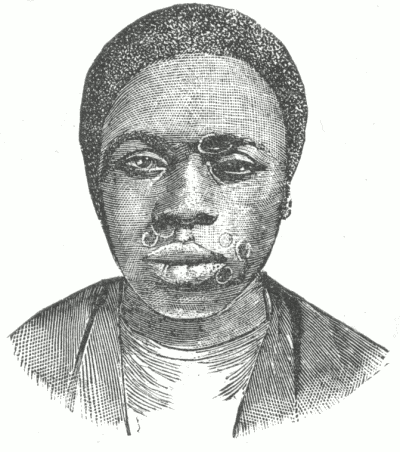

Dermatitis medicamentosa. Bullous dermatitis from iodide of potassium.